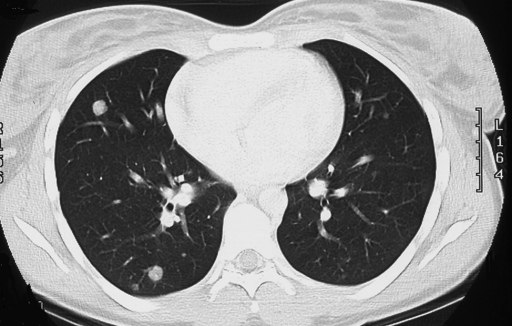

Как рак легких визуализируется на КТ

На томограммах, сделанных в низкодозовом режиме без контрастного усиления, врач-рентгенолог обращает внимание на специфическое уплотнение, хуже пропускающее рентгеновские лучи и в этой связи более светлое на томограммах. Локально отмечаются: усиление сосудистого рисунка, появление одиночных «матовых стекол», а возможно и следов деструкции (повреждения, некроза) здоровых тканей.

О наличии злокачественной опухоли на КТ можно сделать вывод по очаговым изменениям системы кровообращения (уточняется в ходе КТ с контрастом). Растущее новообразование требует больше питания, поэтому рядом с ним как правило наблюдается усиленное кровообращение, появление новых сосудов. Если имеется данный признак, уплотнение с характерными контурами, пациенту рекомендуется проконсультироваться с пульмонологом и онкологом, сдать анализ на онкомаркеры и сделать биопсию.

Метастазы в легких лучше всего визуализируются на КТ-изображениях, поскольку представляют собой участки повышенной плотности в ткани легкого. При этом по наличию других рентгенологических признаков, например, по особенностям кровотока в данной области, врач-рентгенолог сможет определить злокачественный характер изменений.

Метастазы в легких на КТ

Гематогенные метастатические узлы в легких на КТ имеют довольно четко очерченные и ровные контуры. Нечеткие, расплывчатые или лучистые контуры наблюдаются в том случае, если есть инвазивный рост в окружающую легочную ткань. Локализуются преимущественно в нижних, периферических отделах легких, хаотично, без очевидной связи с бронхами и крупными легочными сосудами.

Лимфогенные метастазы легких на КТ выглядят как множественные мелкие диссеминированные очаги. Они расположены вдоль междольковых перегородок и плевры. Картина напоминает туберкулез и саркоидоз, и в этой связи часто требует уточнения. Вместе с лимфогенными метастазами легких почти всегда обнаруживаются патологические изменения (увеличение) лимфатических узлов средостения.

Часто на КТ-сканах визуализируется характерная дорожка к корню легкого. В динамическом наблюдении отмечается инфильтративный рост опухоли.